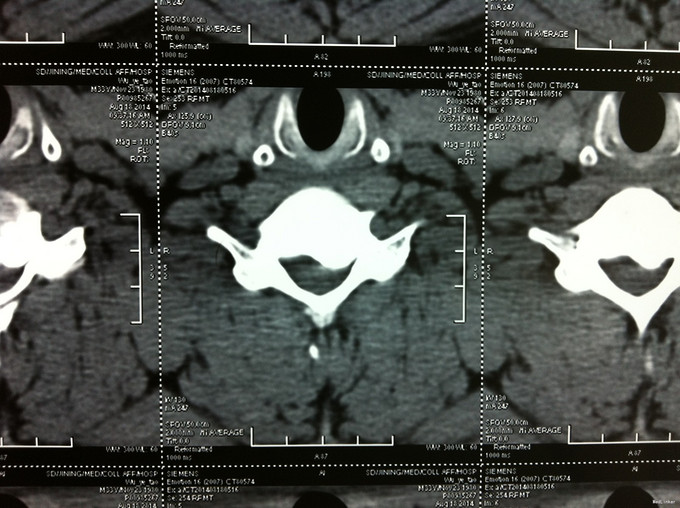

查体:左侧前臂及手感觉减退,右侧正常,左侧伸腕、伸肘肌肌力4级,右侧伸腕、伸肘肌肌肌力4-5级,双侧霍夫曼综合征阳性,双下肢肌张力高,膝腱反射+++,巴氏征阳性,辅助检查: X-ray:劲椎退行性变 CT及MR:颈椎间盘突出,腰5/6,6/7间盘突出并骨赘形成

诊断:脊髓型颈椎病 处理: 1、完善相关辅助检查,明确诊断,有无手术指证; 2、全麻下行颈椎前路减压,颈椎间盘突出并骨赘形成,行颈6椎体次全切,减压较充分。